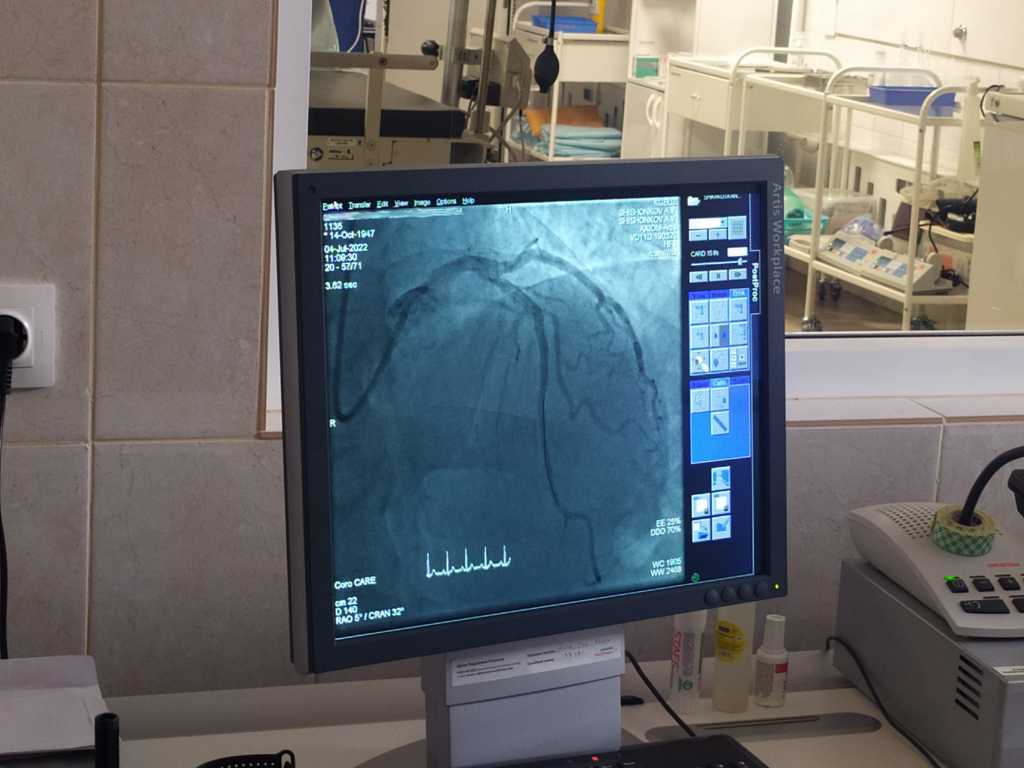

Недавно врачи Красноярской межрайонной клинической больницы №20 дважды спасли жизнь 66-летнему пациенту с артериальной гипертонией и атеросклерозом, который в течение нескольких часов перенёс сначала инфаркт миокарда, а потом ишемический инсульт.

«Несколько лет назад спасти такого пациента было невозможно. Но сегодня при помощи современного оборудования и слаженной работы бригады кардиологов, неврологов и хирургов нам это удалось, - рассказала заведующая неврологическим отделением для больных с острыми нарушениями мозгового кровообращения Наталья Хало. - Этот пациент ранее не проходил обследование и был доставлен к нам с острым инфарктом миокарда, атеросклеротическим поражением сосудов сердца. Ему произвели стентирование коронарных артерий, но через 2 часа у него появилась клиника острого ишемического инсульта. Диагностировали тромбоз крупного сосуда головного мозга. Мужчина снова оказался на операционном столе. Нам удалось восстановить кровообращение и избежать тяжёлых осложнений. Пациент выписан на амбулаторную реабилитацию».

С начала 2022 года полторы тысячи пациентов с инсультами и инфарктами прошли обследование и лечение в региональном сосудистом центре 20-й больницы на современном ангиографе, приобретённом при поддержке национального проекта «Здравоохранение». Оборудование экспертного класса позволяет достаточно четко диагностировать проблему, отслеживать состояние пациента в динамике и выполнять операции, о которых раньше врачи могли только мечтать. К примеру, диагностическая коронарография длится всего 15-20 минут, проводится под местным наркозом, пациент находится в сознании.